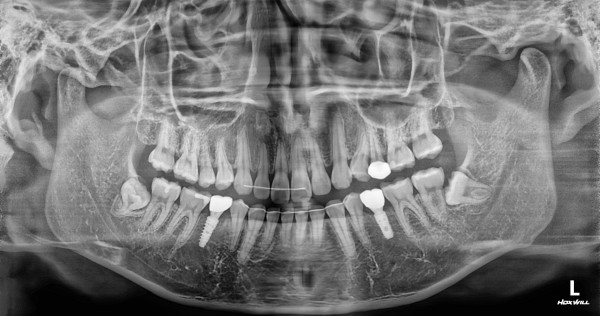

임플란트 센터 | 여) 23세